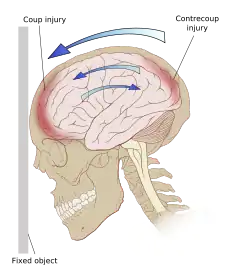

Damage may occur directly under the site of impact, or it may occur on the side opposite the impact (coup and contrecoup injury, respectively).[65] When a moving object impacts the stationary head, coup injuries are typical,[69] while contrecoup injuries are usually produced when the moving head strikes a stationary object.[70]